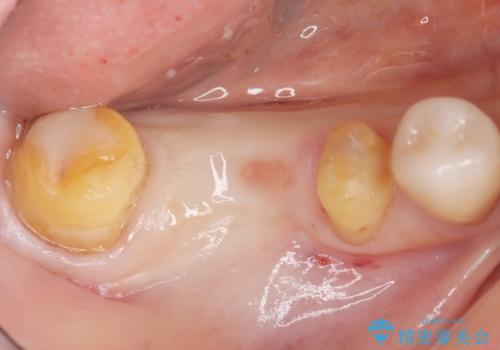

右下の銀歯(右下6)を除去したところ、虫歯が深く保存不可能な状態でした。

ブリッジ、インプラント、入れ歯の3つの選択肢を提案したところ、ブリッジをご希望されました。

抜歯後十分に歯肉の治癒を待ったのち、ブリッジによる補綴治療を行いました。